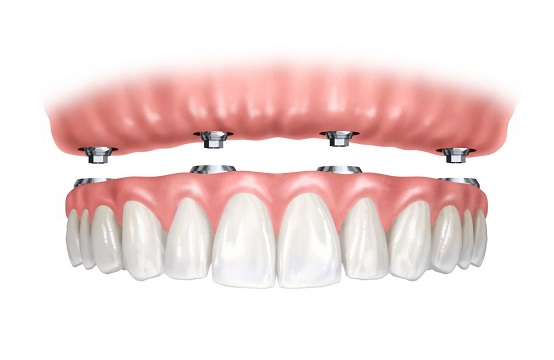

To je sistem uz pomoć kog sa samo 4 implantata moze da se reši bezubost, tj dovoljna su samo 4 implanta da bi imali sve zube u jednoj vilici.

Zato što predstavlja najpouzdaniji i najbolji izbor terapije kod rešavanja potpune bezubosti. Zato što je naučno dokazano da na strateški izabranim mestima 4 implanta obezbedjuju istu i bolju stabilnost od 6-10 koliko ih se najčešće postavlja. Zato što je ALL ON 4 najbrži način da dobijete fiksno protetsko rešenje. Privremene zube dobijate već u roku od 2 dana od ugradnje implantata.

Nakon preoperativnih priprema, ako je potrebno, izvade se preostali malobrojni zubi (ako ih ima i loši su), i postavljaju se na tačno utvrdjena mesta posebni implanti, vodeći računa o okolnim anatomskim strukturama. Dva implanta se postavljaju u frontalnu regiju gde je volumen kosti veći, i gde se očekuje najmanja atrofija kosti, a druga dva implanta se postavljaju u bočnoj regiji pod uglom od 45 stepeni, kako bi budući zubi bili stabilniji, vodeći računa o bitnim anatomskim parametrima, tj maksilarnom sinusu u gornjoj i mandibularnom kanalu u donjoj vilici.